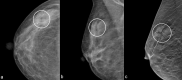

Radial scar (RS) or complex sclerosing lesions (CSL) if > 10 mm is a benign lesion with an increasing incidence of diagnosis (ranging from 0.6 to 3.7%) and represents a challenge both for radiologists and for pathologists. The digital mammography and digital breast tomosynthesis appearances of RS are well documented, according to the literature. On ultrasound, variable aspects can be detected. Magnetic resonance imaging contribution to differential diagnosis with carcinoma is growing. As for the management, a vacuum-assisted biopsy (VAB) with large core is recommended after a percutaneous diagnosis of RS due to potential sampling error. According to the recent International Consensus Conference, a RS/CSL lesion, which is visible on imaging, should undergo therapeutic excision with VAB. Thereafter, surveillance is justified. The aim of this review is to provide a practical guide for the recognition of RS on imaging, illustrating radiological findings according to the most recent literature, and to delineate the management strategies that follow.